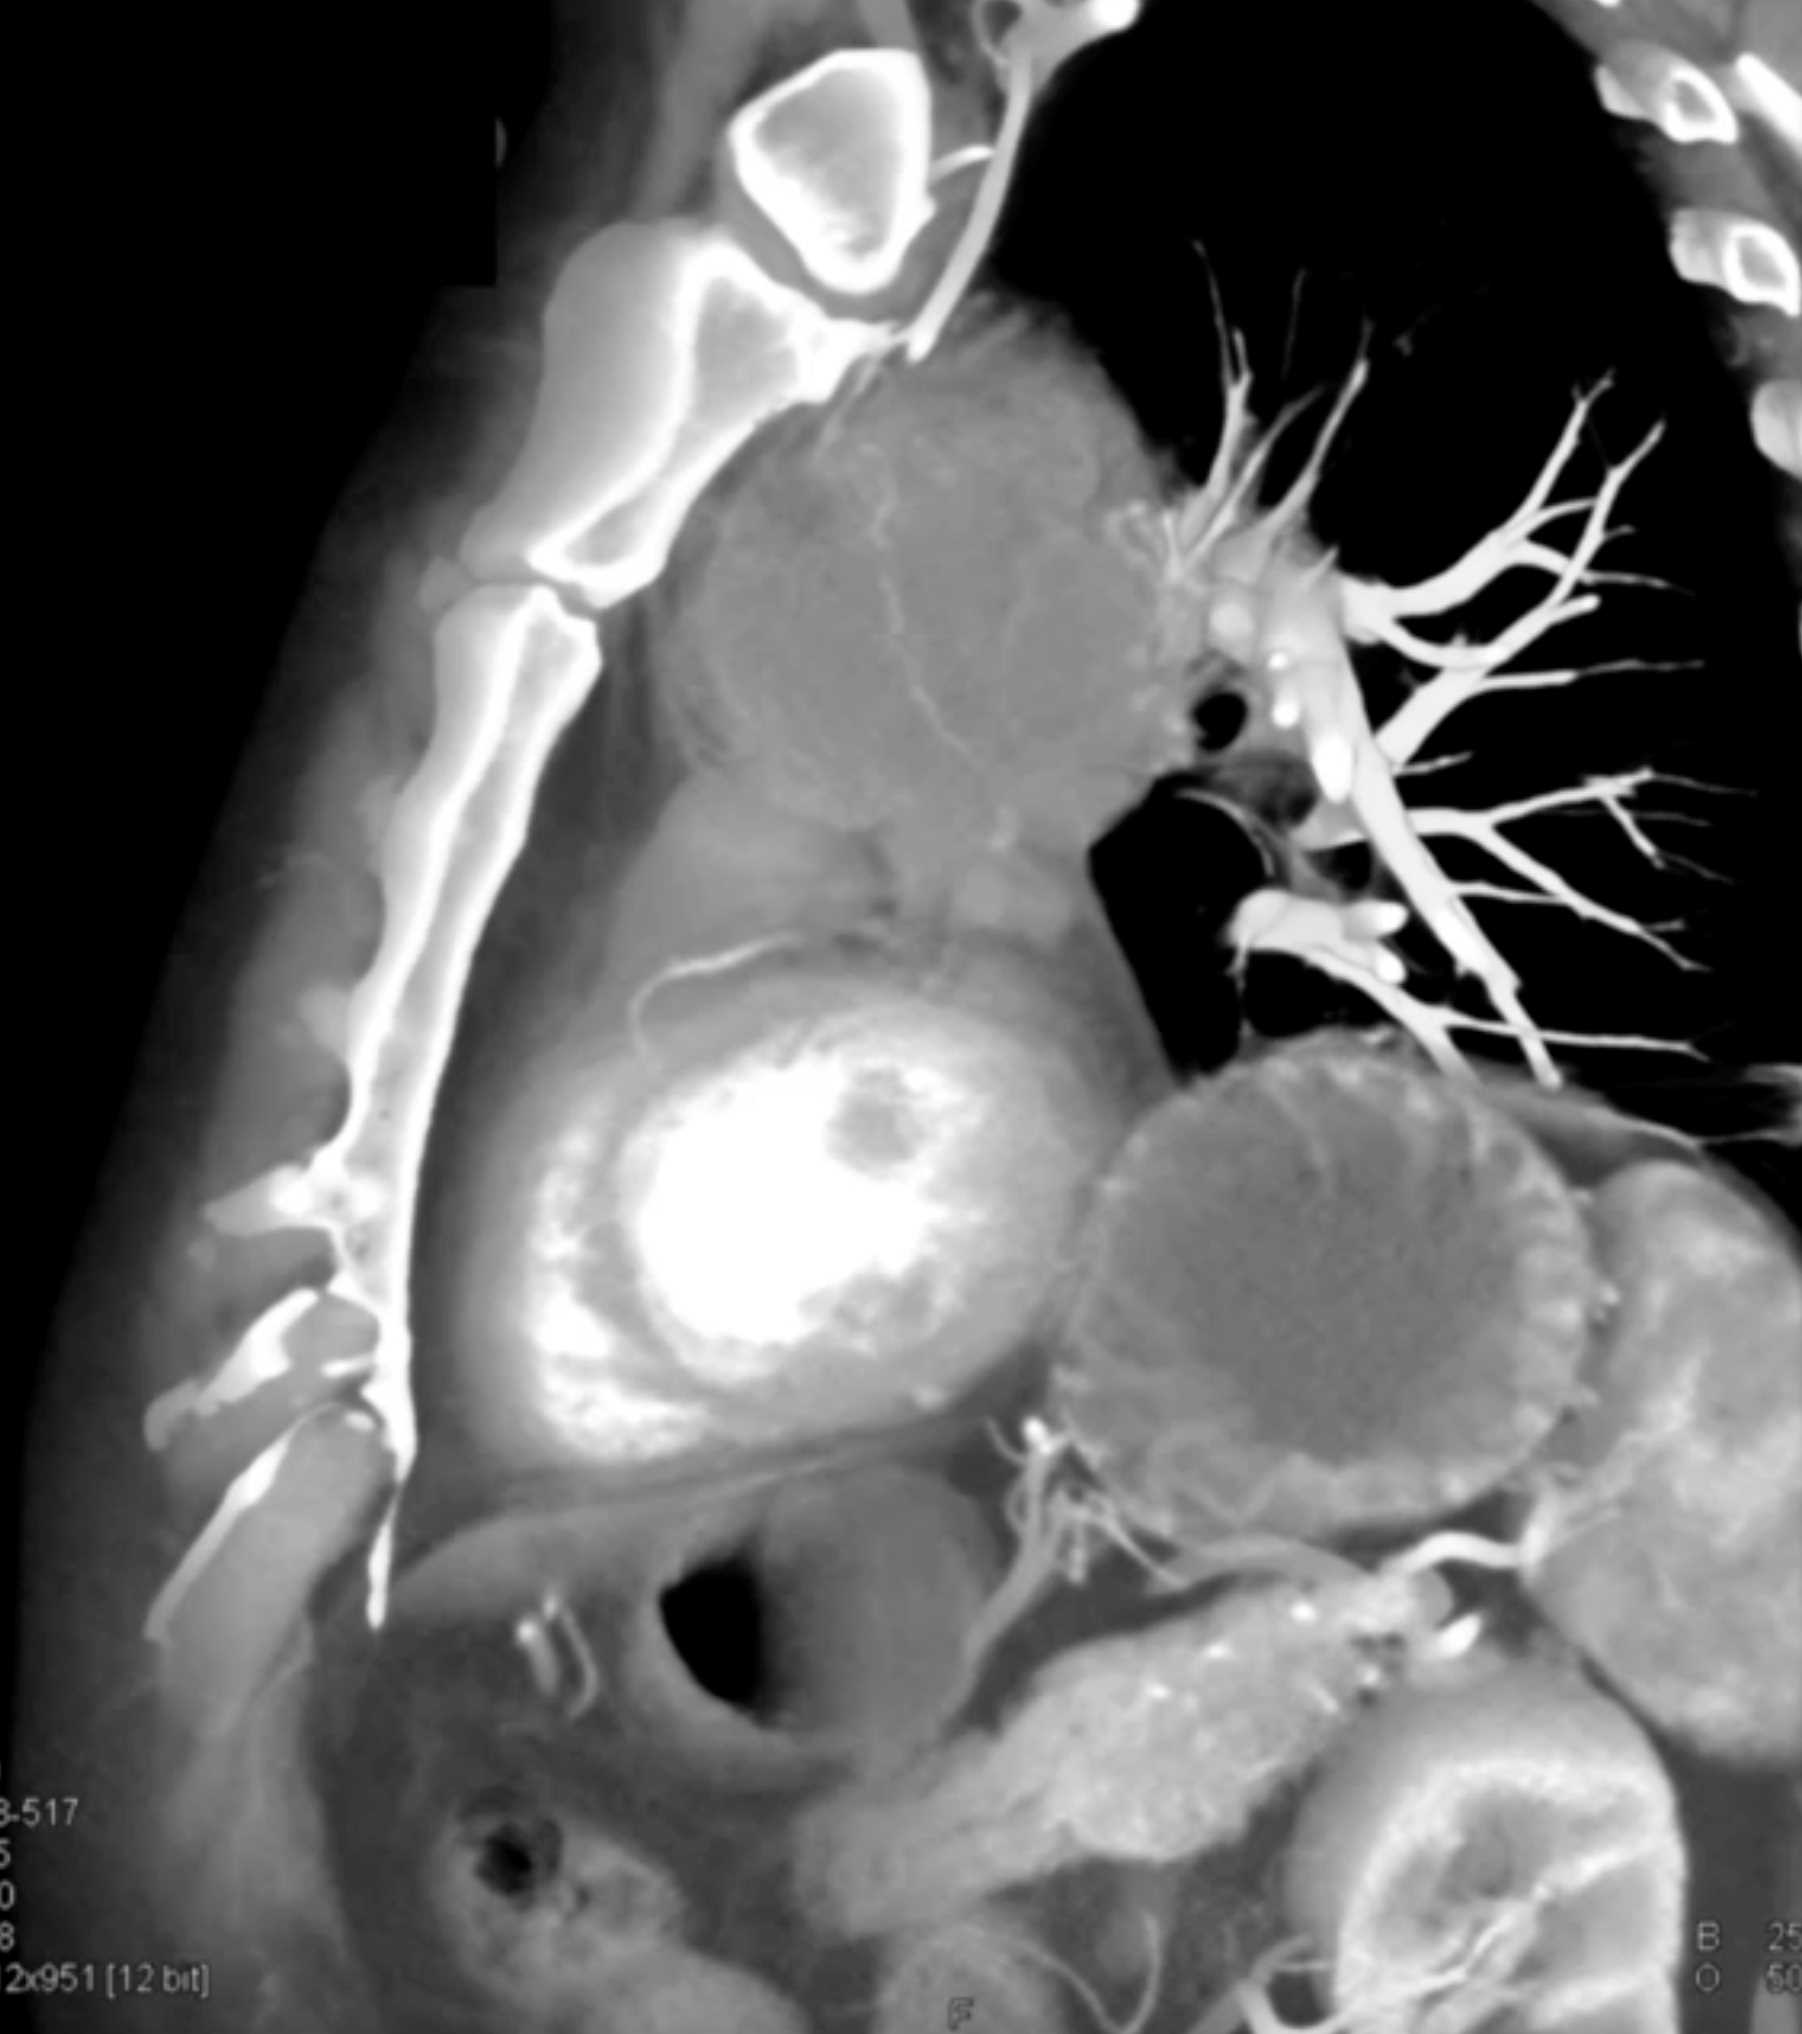

Thymic Carcinoma